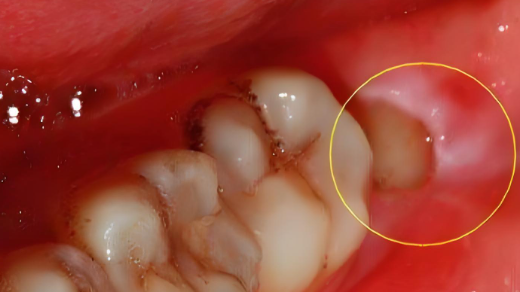

因为横生智齿和第二磨牙挨得很近,中间容易卡食物,时间长了会发炎